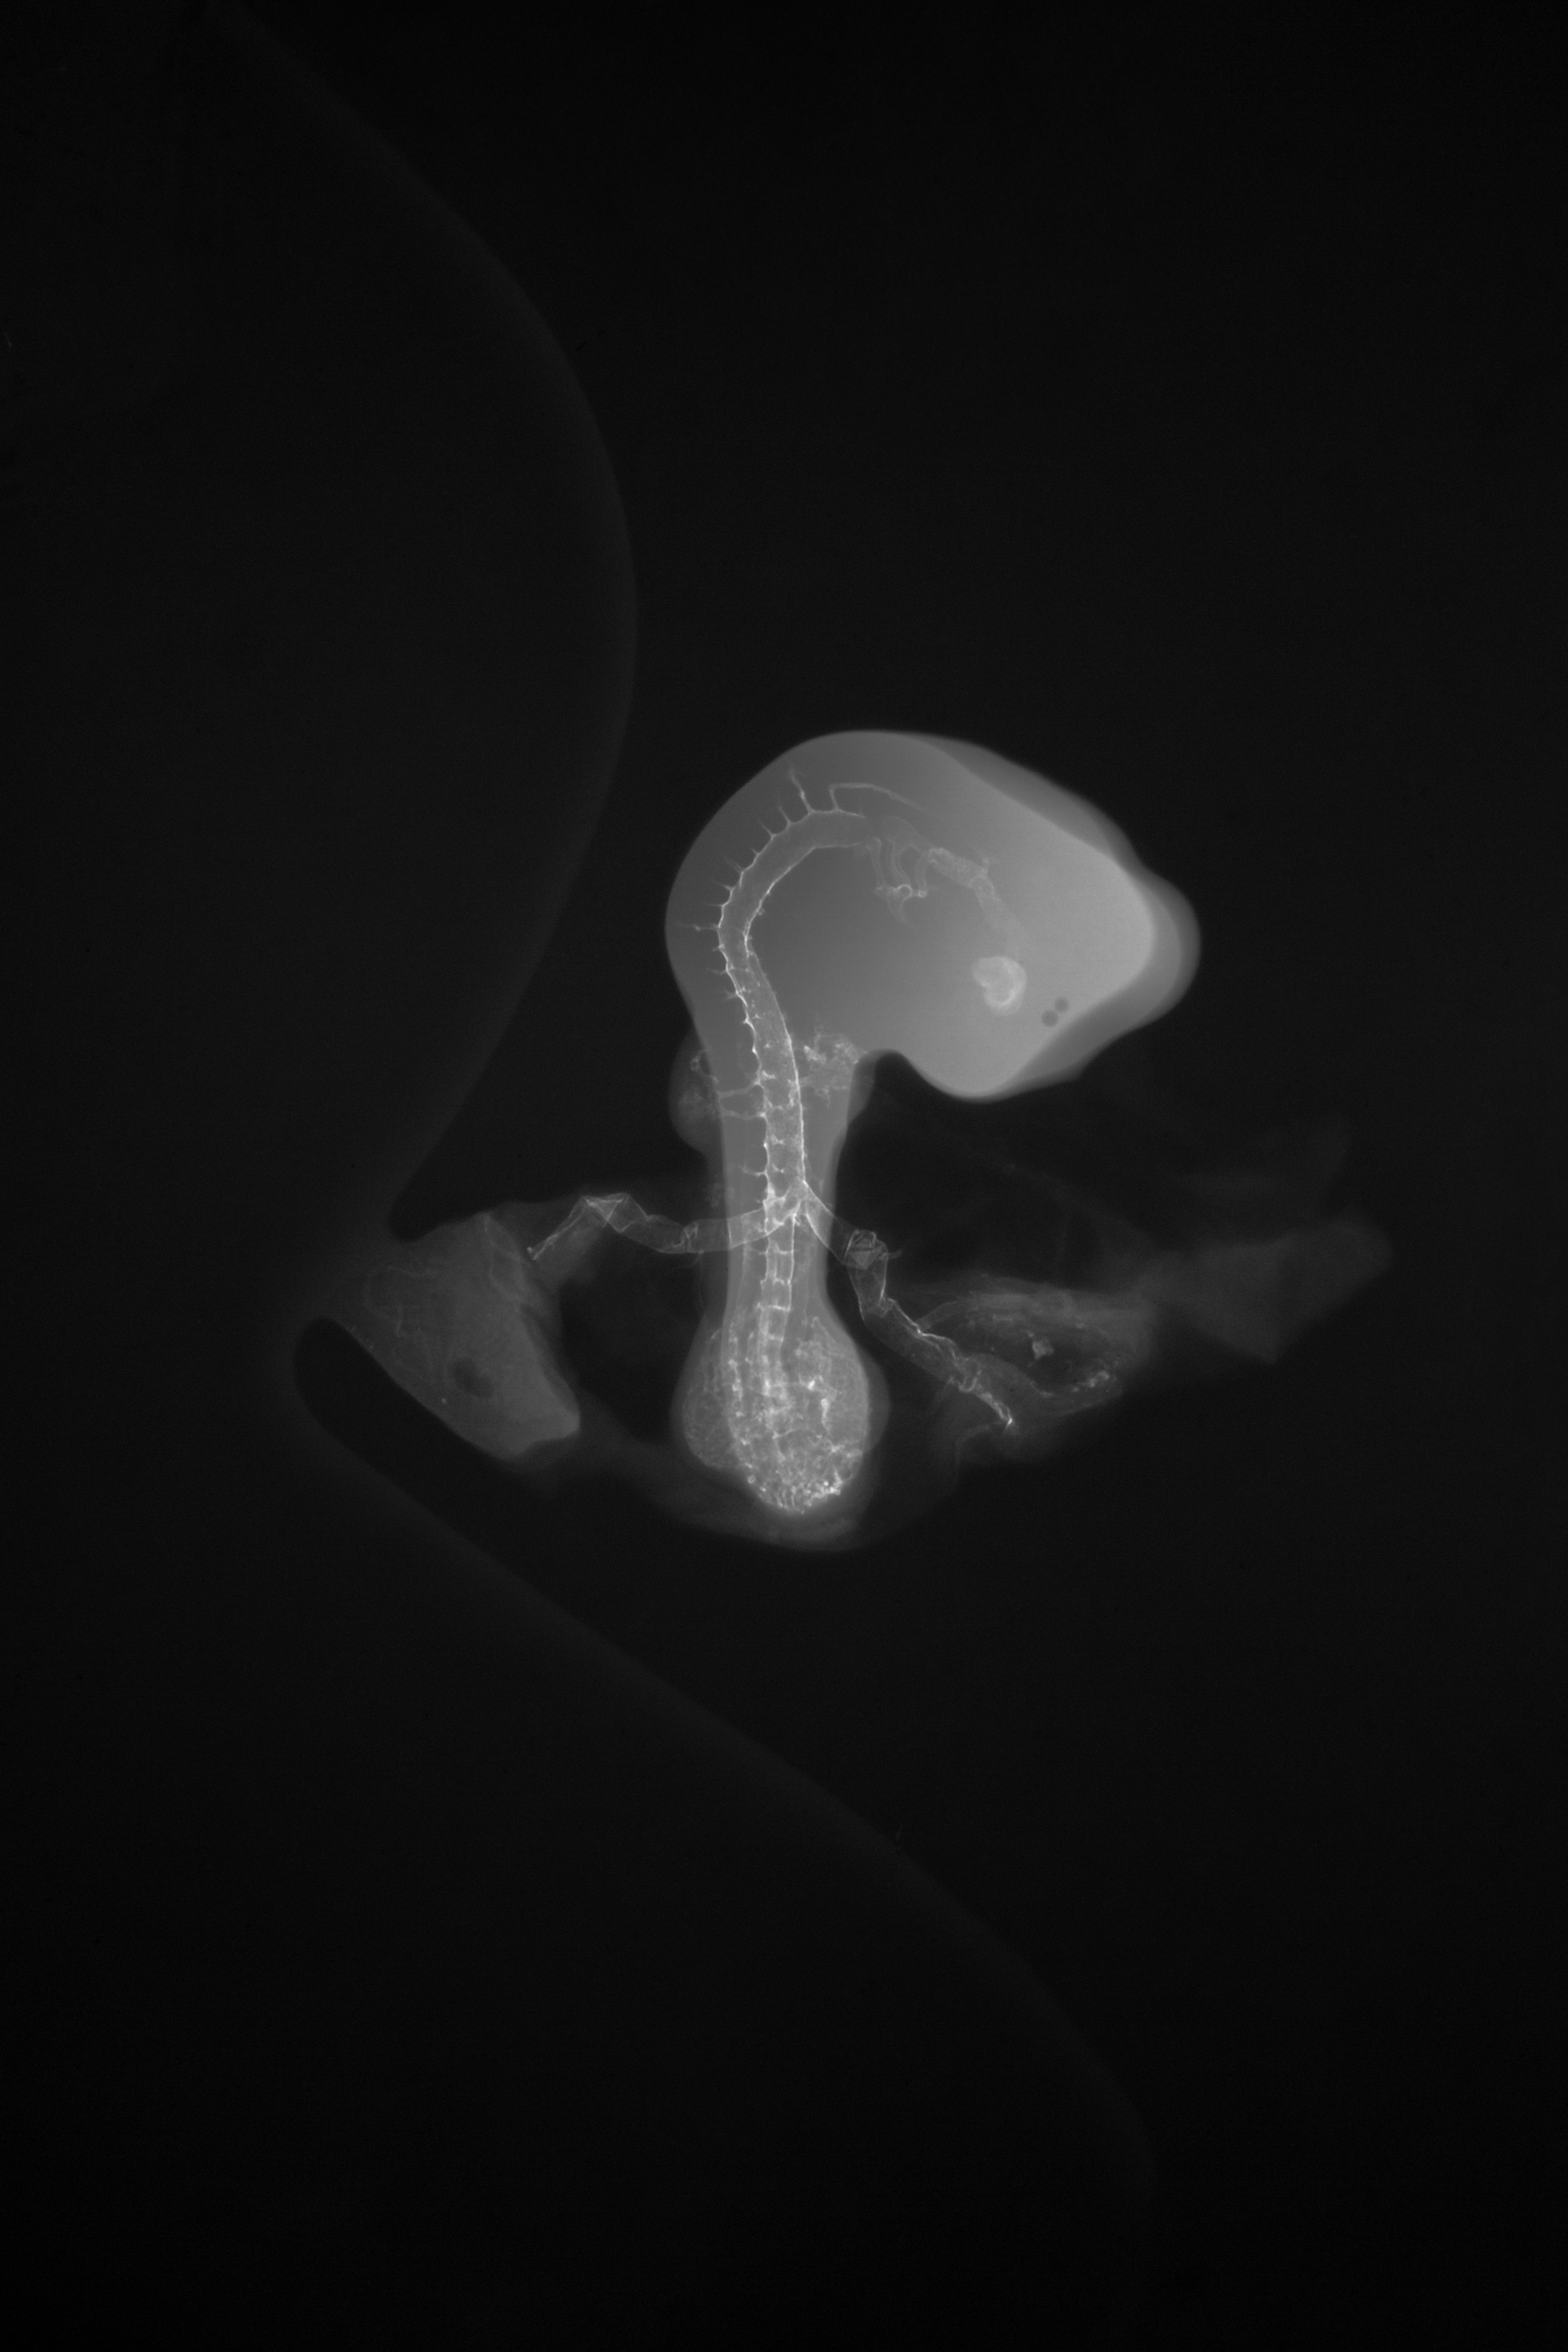

Hamburger-Hamilton (HH) Stage 20 (approx. 3 - 3.5 days)

X-Ray Micrographs